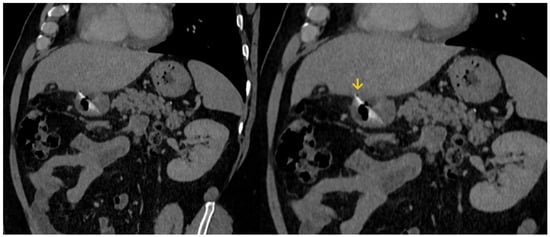

2. Case Report